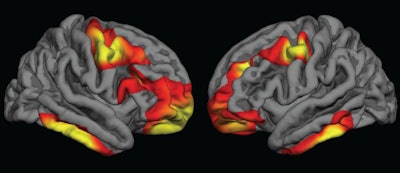

The researchers observed cortical thickness in the bilateral frontal and inferior temporal regions of the brain in adolescents who were exposed to folic acid compared with those who were not. For children born during the fortification period, partial folic acid exposure had more "intermediate effects," they noted.

The differences were characterized by significantly thicker brain tissue and delayed thinning of the cerebral cortex in regions associated with schizophrenia.

Within the MGH cohort of normal brain scans, the researchers "observed widespread increases in frontal and temporal cortical thickness between comparable groups of youths who gestated just after, compared with just before, the rollout of folic acid fortification," they wrote. "Youths who gestated during the [folic acid] rollout, and who therefore had partial exposure, demonstrated intermediate increases, consistent with a dose association."

Results from the PNC subjects were similar to those in the MGH adolescents, with individuals exposed to folic acid fortification showing signs of delayed cortical thinning of similar duration in the frontal, temporal, and parietal regions.